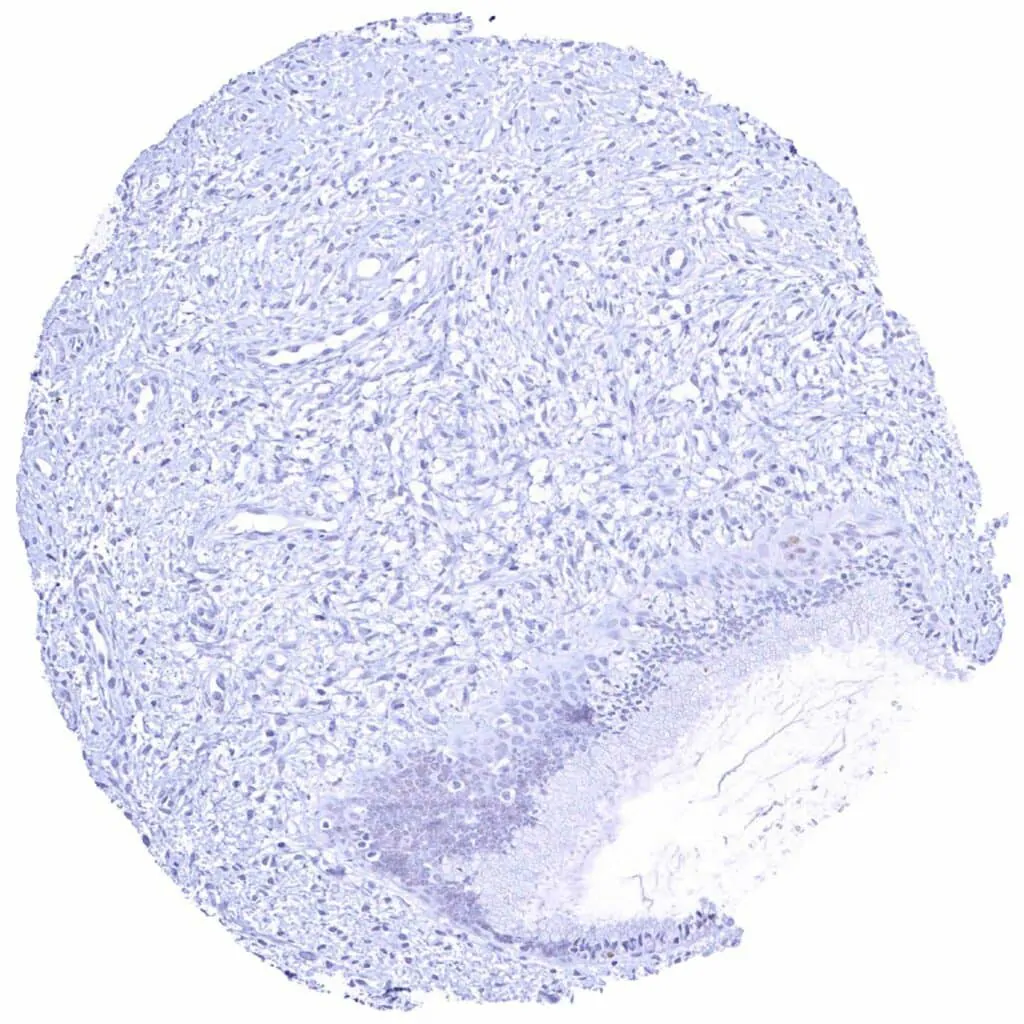

Urinary bladder, muscular wall